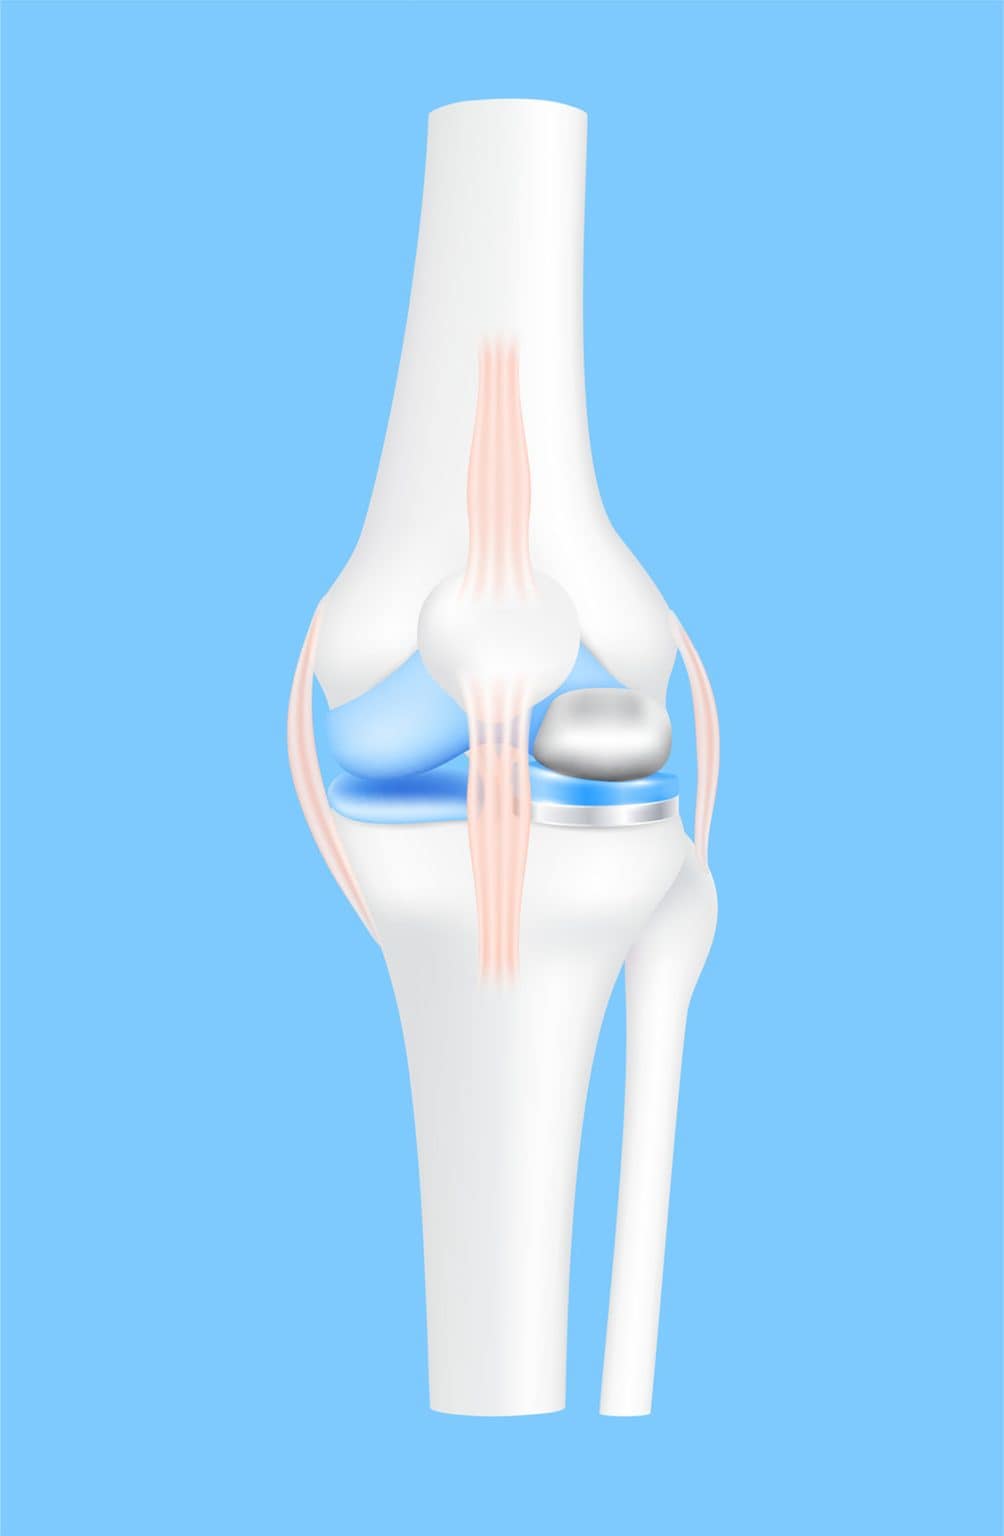

The Oxford Partial Knee System was developed to address two challenges that affected older partial knee replacement designs: implant loosening and plastic insert wear. In traditional fixed bearing designs, the knee’s twisting motion is repeatedly channelled through one fixed contact surface during everyday activity. As the knee bends and rotates, this twisting load is repeatedly transferred into the cement that holds the implant to bone, which can strain the bond and reduce long term fixation strength.

For this reason, the Oxford Partial Knee System uses a mobile bearing design, where controlled movement is built into how the implant works. Instead of locking the plastic insert in place on the tibial base, the insert is designed to float and move freely on top of it as the knee bends and rotates. This allows everyday twisting forces to be absorbed through the insert’s mobility, rather than being repeatedly transferred into the cemented fixation. And since the insert surface is shaped to match the curve of the femoral component closely, load is spread across a broader area instead of being concentrated in one spot. This is made possible through the implant’s key components working together.

The Oxford Partial Knee System consists of three components that work together inside the treated knee compartment:

Rather than acting as separate parts, these components are designed to work together as the knee bends, straightens, and rotates under load. And this design is what supports the three key things patients tend to care about most: